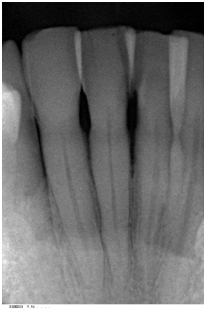

A 72 year-old white male was referred due to an isolated increasing probing depth on the disto-facial aspect of the mandibular right lateral incisor which had an initial PD of 10 mm with BOP (Table 2). Increase in probing depth is illustrated in the clinical photo (Figure 6). The patient was seen for a comprehensive periodontal examination and a periodontal maintenance visit after scaling and root planing was previously performed. His oral hygiene and plaque control was very good and no local factors were detected at that time. Radiographic evaluation revealed a slight radiolucency on the distal of tooth #26 (Figure 7).

Figure 7 Pretreatment radiograph of tooth #26 revealed a slight radiolucency on the distal aspect.

Supportive periodontal therapy was performed on a regular basis starting 6 weeks after surgery and every three months making sure not to instrument the surgical site subgingivally. The patient’s plaque control was optimal. The patient was recalled 6 months after surgery. Full mouth periodontal charting was completed. The disto-facial surface of tooth #26 exhibited a remarkable reduction in PD and BOP (Table 2). The patient was pleased with the esthetics and function. 12 months follow up was performed that revealed stable periodontal readings when they were compared with the 6 months readings. At the 12 month reevaluation, the PD was 3mm at the disto-facial surface of #26. There was a CAL gain of 6 mm (Figure 9) (Figure 10). Table 2 present clinical measurements at baseline, 6 and 12 months and documents a tendency for continued improvement in PD and CAL from baseline.

Figure 10 Periapical radiograph of tooth #26 taken 12 months after surgery.